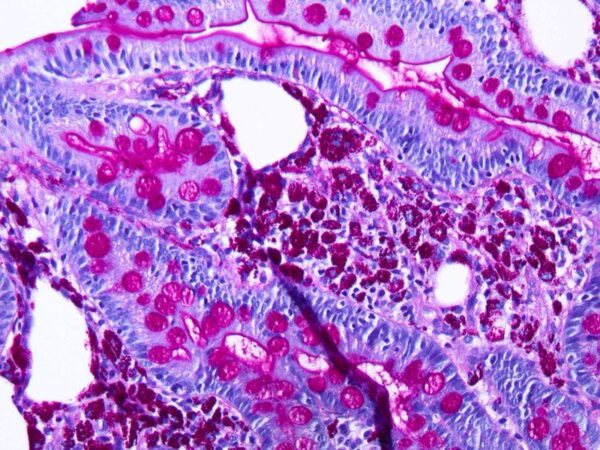

- En histología y citología, se tiñen las muestras con colorantes específicos para resaltar componentes celulares o tisulares de interés. Sin embargo, la simple observación de la coloración no siempre es suficiente para confirmar la identidad del componente.

- La digestión enzimática se utiliza como una técnica adicional para confirmar que la coloración observada realmente corresponde al componente de interés. Por ejemplo, si una muestra está teñida en azul para resaltar el glucógeno, la aplicación de amilasa permitirá degradar el glucógeno, eliminando la coloración azul. Si el componente era realmente glucógeno, la coloración desaparecerá.

- Esta técnica es especialmente valiosa para identificar componentes celulares específicos, como almidón, glucógeno, ADN o ARN, en muestras biológicas. Permite una caracterización precisa de la naturaleza de estos componentes y su distribución en células y tejidos.